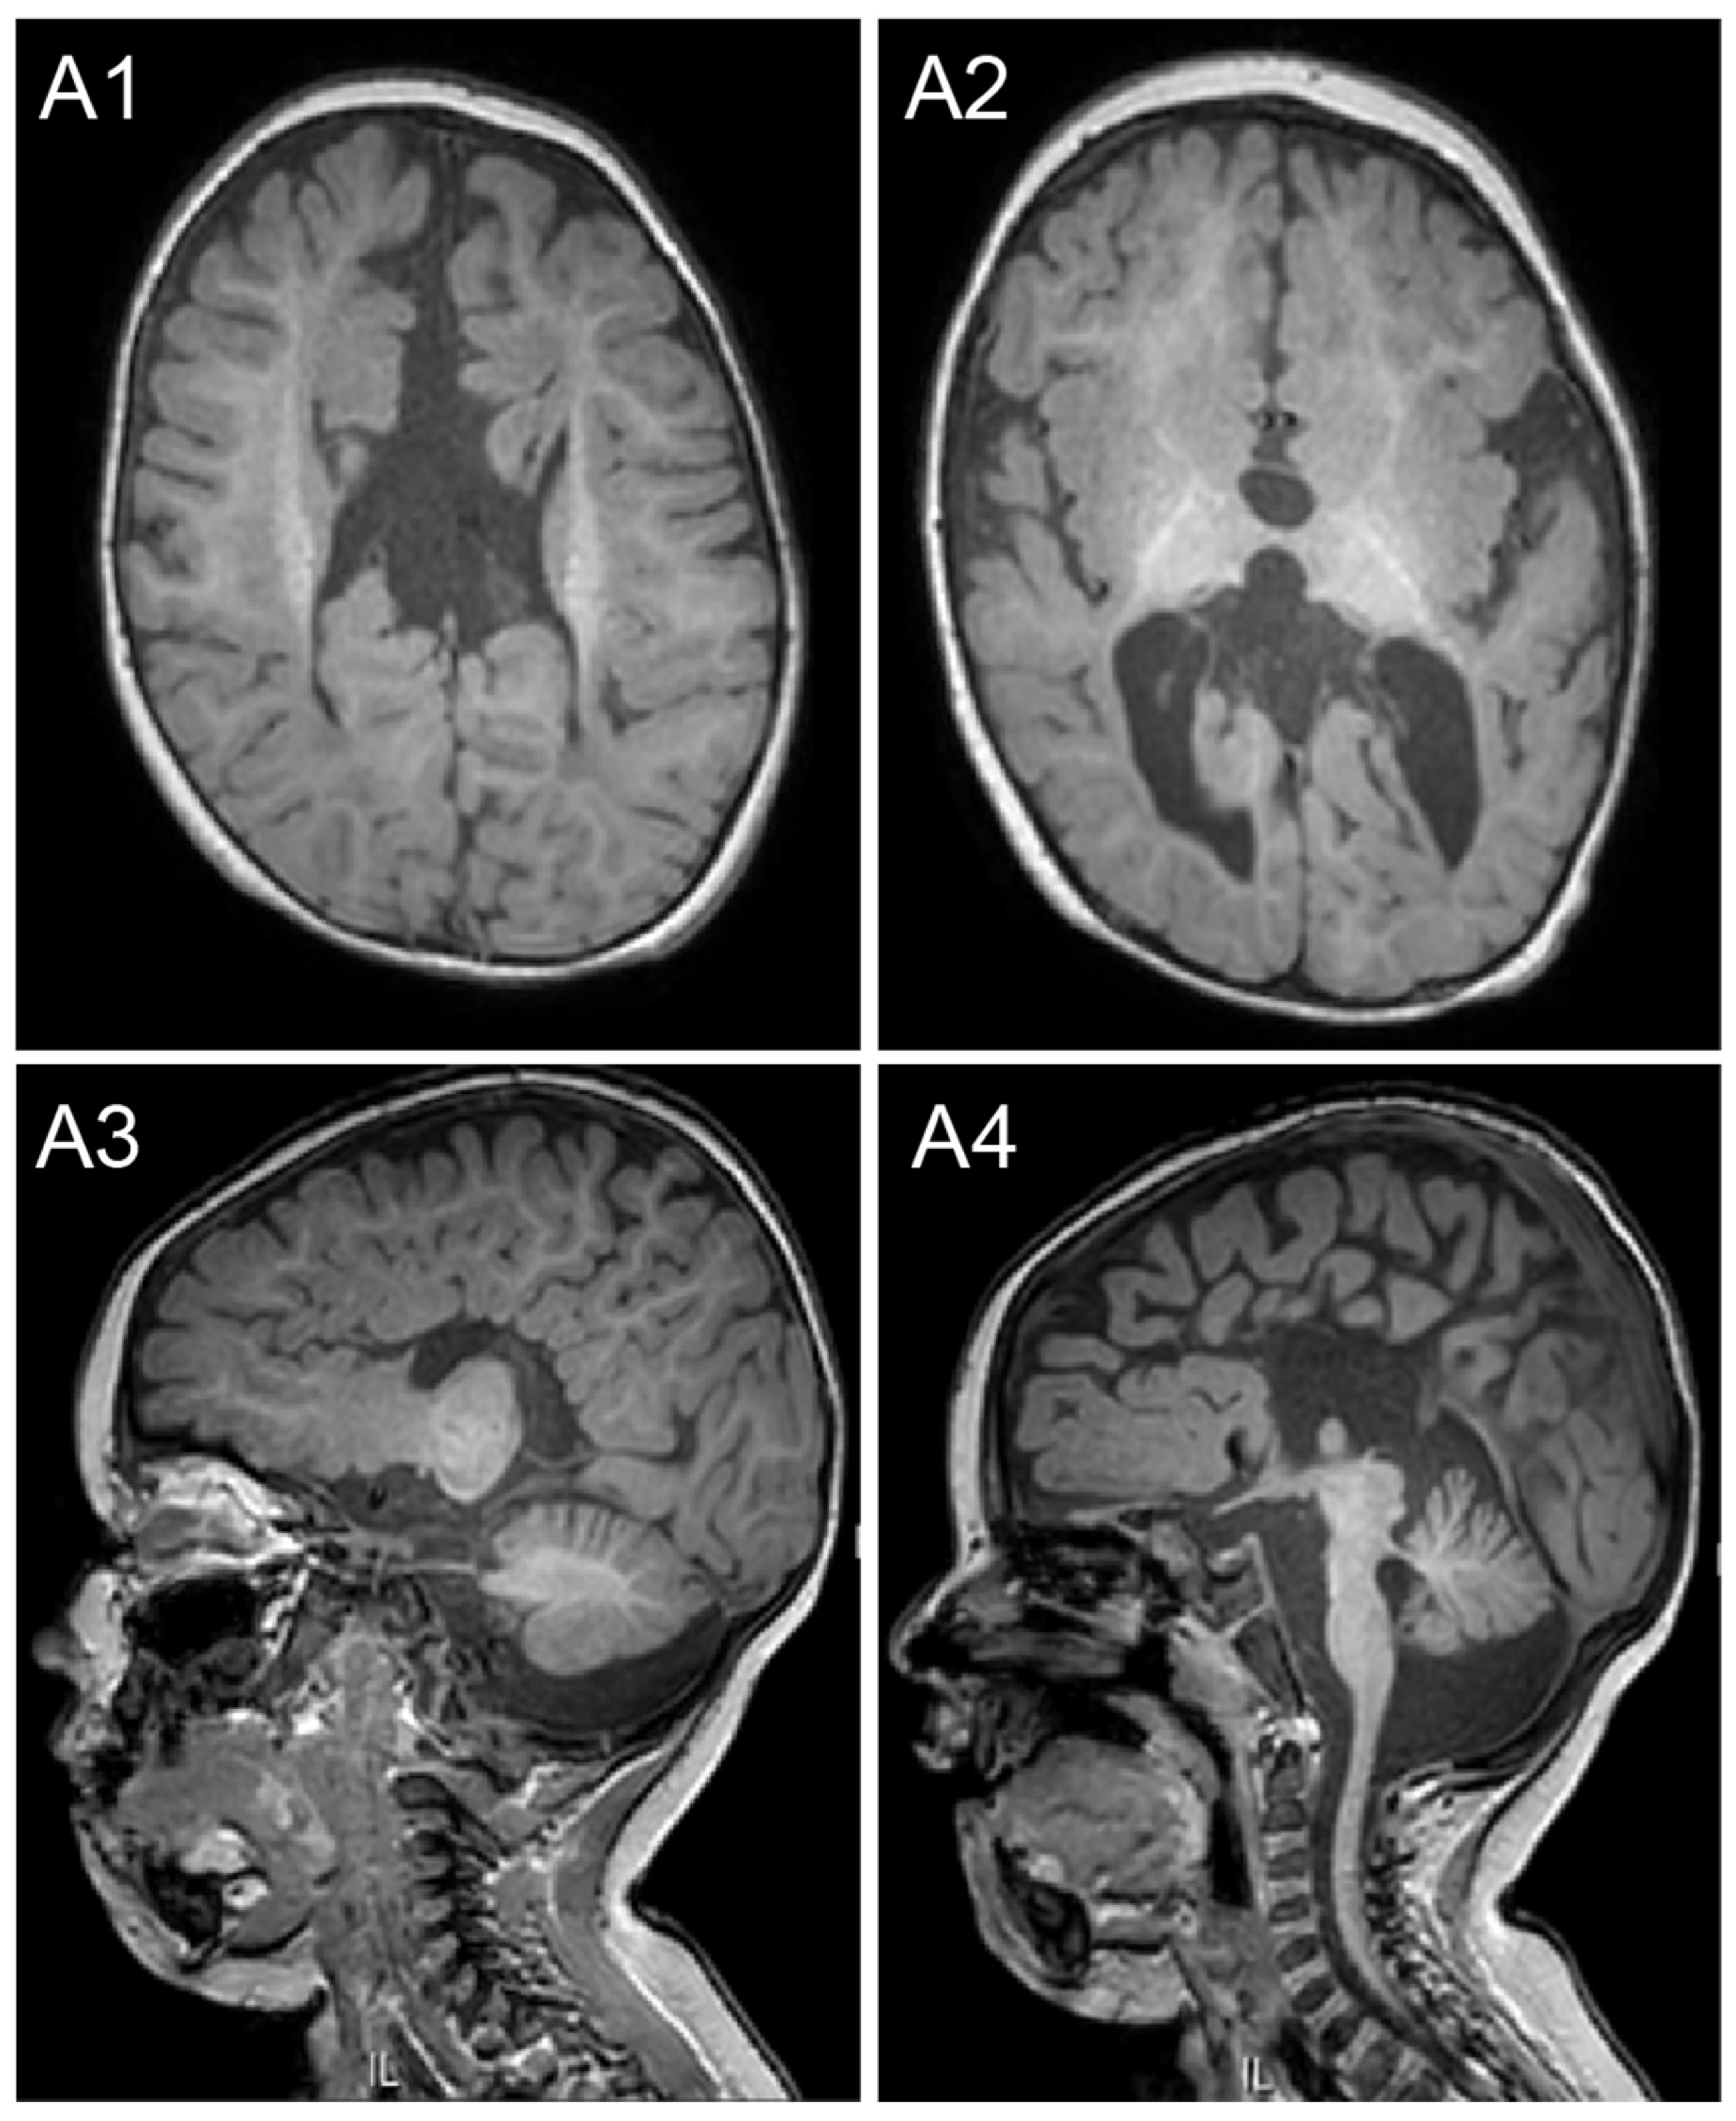

| Corpus callosum agenesis | Yes | No | Not available | Yes | Yes | Yes (4/4) | Yes (2/2) |

| Cerebral findings | Pronto-cerebellar volume reduction and white matter abnormalities | No | Not available | Polymicrogyria in the insula, agenesis of the posterior corpus callosum, and pyramidal tract hypoplasia | Cerebral and cerebellar cortical atrophy | Frontoparietal cortical atrophy (3/3) | No (2/2) |

| Ventriculomegaly | Yes | No | Not available | No | No | Yes (2/3) | Yes (2/2) |

| Microcephaly | Yes | No | Yes <1st percentile | No | No | Yes (2/3) | Yes (2/2) |